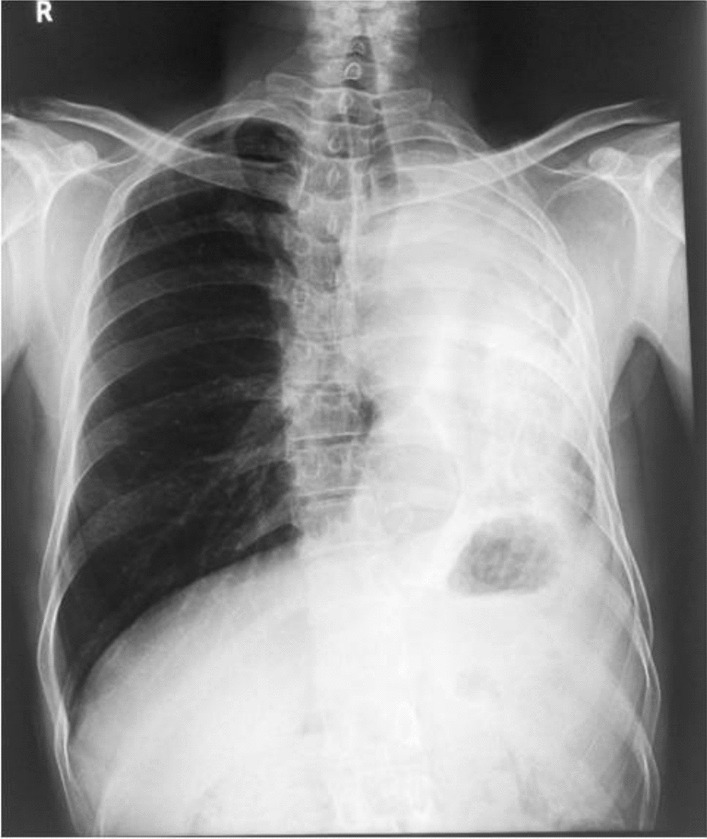

On physical examination, he had normal vital signs and was cachectic. On respiratory examination, he had decreased air entry on the left side. A chest radiograph revealed a heterogeneous opacification of left hemithorax, ipsilateral shift of mediastinum, elevation of left hemidiaphragm, crowding of ribs on left, and hyperinflation of the right lung (Fig. 1). These features were suggestive of volume loss of the left lung. There was a bronchial cut-off sign on the left. There was minimal blunting of the left costophrenic angle. The right costophrenic angle was normal.

Fig. 1.

Chest radiograph shows heterogeneous opacification of the left hemithorax with an ipsilateral shift of mediastinum and loss of left lung volume. There is an elevation of the left hemidiaphragm with crowding of ribs and hyperinflation of the right lung